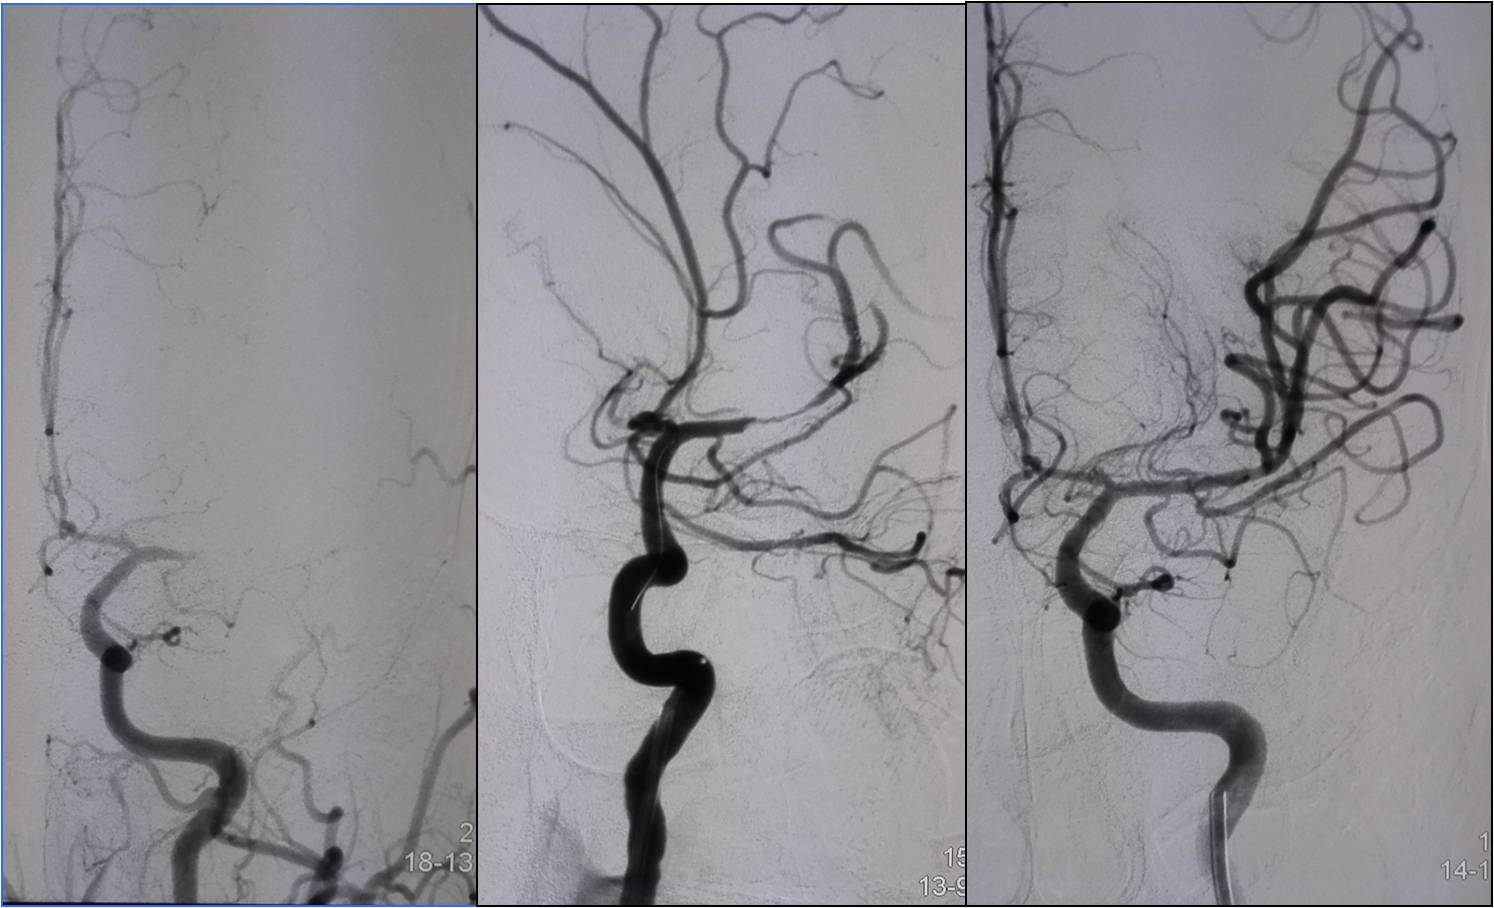

Case6 术后呼吸功能衰竭

》54岁,男,既往脑梗死、高血压病、糖尿病

》因头晕伴呕吐2天,9:50到达急诊

》10:08完成头CT检查

》15:30突发心跳骤停,行心肺复苏、气管插管

》NIHSS 30分

》15:55头MRA检查

》17:00行股动脉穿刺

》18:50结束手术

》术后24h NIHSS 10分

▼左椎动脉颅内段闭塞,脊髓前动脉代偿

▼右椎动脉颅外段闭塞

▼取栓后左椎动脉V4段残留狭窄

▼球囊成形,狭窄改善,不能维持

▼Wingspan支架置入

》11.30 13:00拔气管插管后不能呼吸,呼吸动度差,面部青紫,重新插管,spO2最低20%,意识不清,2小时后恢复。

》12.3 10:00再次拔管后仍不能呼吸,插管

》12.3 16:00行经皮气管切开。

》12.5 转普通病房后因血压高应用硝普钠后血压降至50mmHg,呼吸困难,青紫,昏迷,应用呼吸机后意识恢复。

》12.14自动出院,12.15死亡